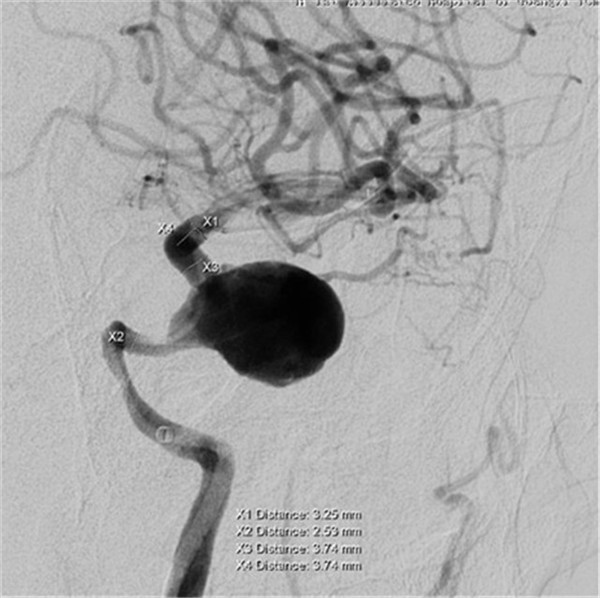

患者是一位70岁的女性,已视物重影1年余,经外院检查确诊为“左侧颈内动脉海绵窦段巨大动脉瘤伴瘤内血栓形成”,医生告知因动脉瘤位于海绵窦内,瘤颈宽约8mm,大小约2.8×2.3×2.2cm,传统手术方法无法完成动脉瘤夹闭或栓塞治疗,同时手术创伤大、风险高。听了医生的话患者不得不放弃手术。

最近,患者因症状加重来到Beat365中国唯一官方网站第一附属医院求治。该院神经外科张高炼主任主持的治疗团队对该病例进行了讨论和分析,因影像学检查显示动脉瘤载瘤动脉明显迂曲且血管直径较细小,覆膜支架系统通过可能较困难且易引起载瘤血管损伤或动脉瘤破裂出血,他们决定利用密网支架技术行颅内巨大动脉瘤封堵技术为患者治疗。新技术的开展经汇报后得到院领导的大力支持,医院为此简化医疗药械申购手续,购买由美国eV3公司生产的Pipeline血流导向装置(密网支架系统),并邀请到中美合作上海德济医院院长宋冬雷教授前来会诊和指导。

术前DSA